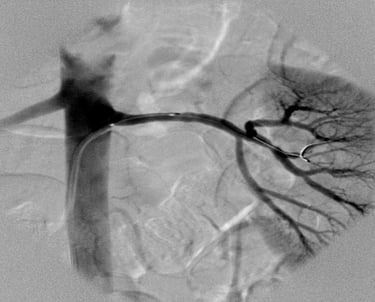

65 years old man from Azamgarh came to me with severe chest pain post CABG which was done in 2021.....

Patient was immediately taken for coronary Angiography which shows LIMA was 100% blocked which was stented Patient was completely pain free since then and living a good quality of life Today he came to meet me in my OPD in tamkuhi raj with smiling face....